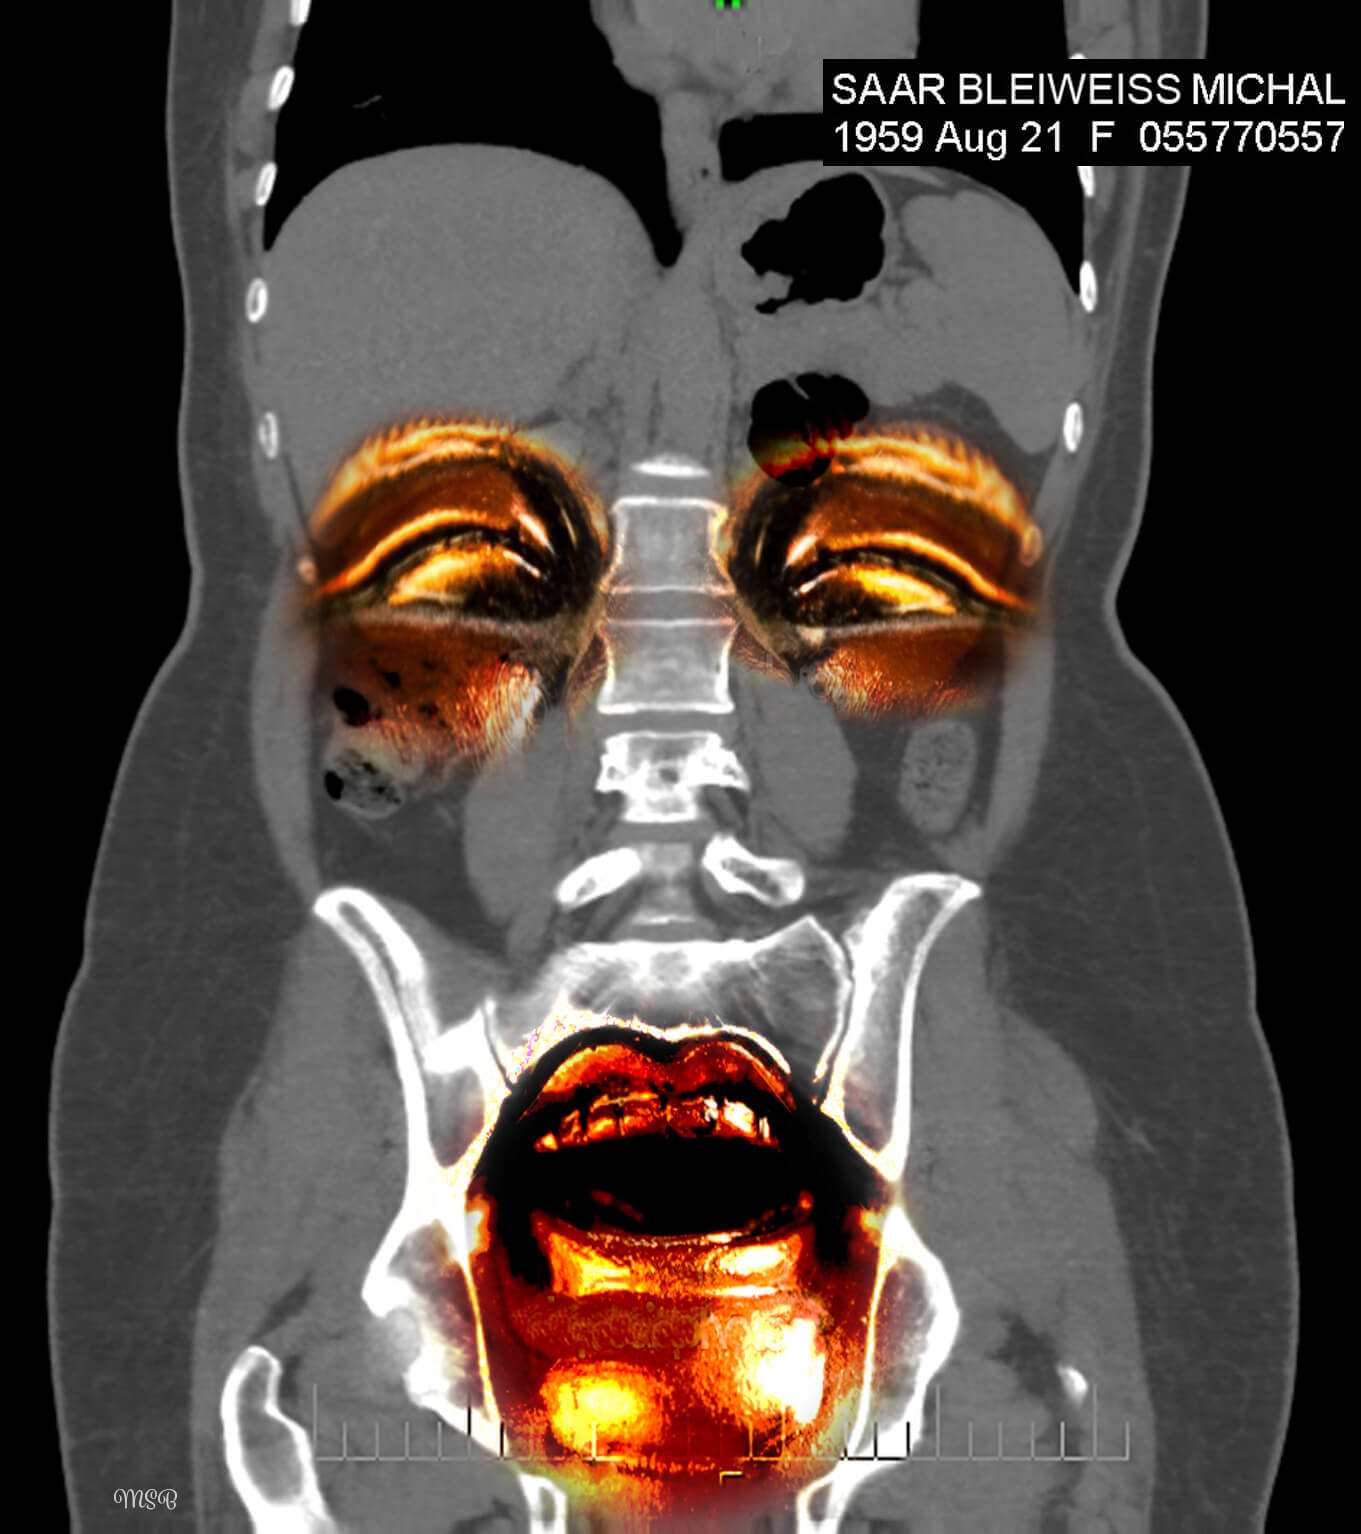

A reimagining of “self,” by Michal Saar-Bleiweiss

A few years ago, I became ill with Nephrostomy and had to undergo surgery. I was sitting with my husband, Mark, at a clinic in Ramat Aviv, Israel, in the office of a professor who specializes in CT* decoding. There, on two huge screens, for the first time I saw my body from the inside, and it was at this moment that my creative impulse arose.

The images before me were entirely in black and white, devoid of personality or character. There was no sign of the Michal that was me, and I felt a great desire and need to take these images to reinstate Michal, the person. When we returned home, I was curious about how I would feel when I looked at the images again—but this time on my computer screen. What I saw created an emotional storm within me.

This storm opened my “third eye,” enabling me to look inside myself. In my imagination I saw colors, dimensions, and expressive features, such as eyes. This was probably my way of internalizing my new reality, digesting what is going on inside me and brushing off my fears and pain. I wanted and needed to wake up each morning with a new smile and the ability to cope.

Having released the pain from the CT images, I found myself opening the next chapter in my imagination—creating digital collages.